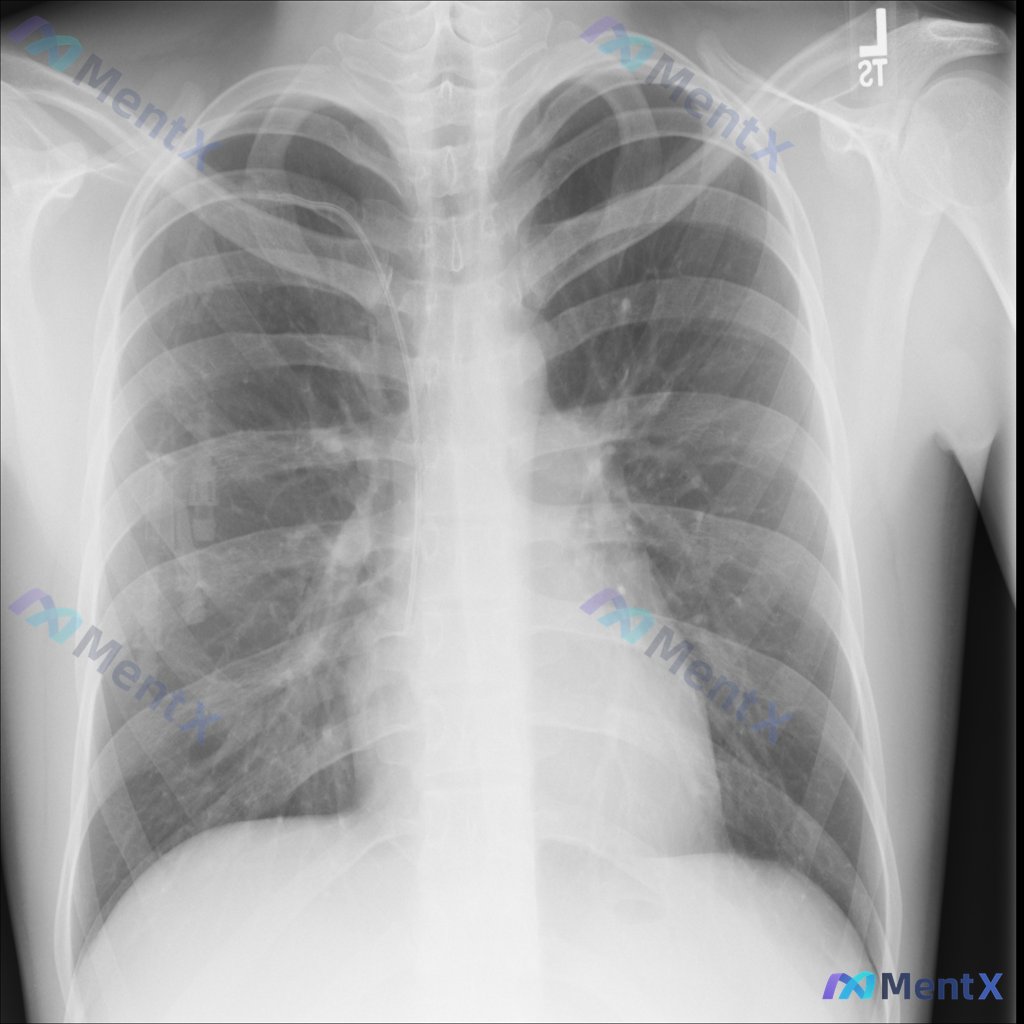

基础情况:影像为床旁前后位胸片,右侧肺野可见管路影,右侧腋下有电极片伪影。

核心影像发现:

- 右肺野中上部(接近第3-4前肋间)可见一较明显的类圆形高密度结节影,边界相对清晰

- 右侧胸壁/肺野有管路影(提示可能为深静脉置管或引流管)

- 其余:气管居中,纵隔不宽,心影正常,未见大片实变/积液/气胸,所示骨质未见明确破坏

📋答案:该病例核心思路应优先建立「右肺结节与右侧管路的因果关联」,第一优先级排查导管相关并发症(如导管移位/异位、药物外渗性肉芽肿、导管周围异物反应等),同时尽快完善胸部HRCT检查明确结节细节与空间关系。